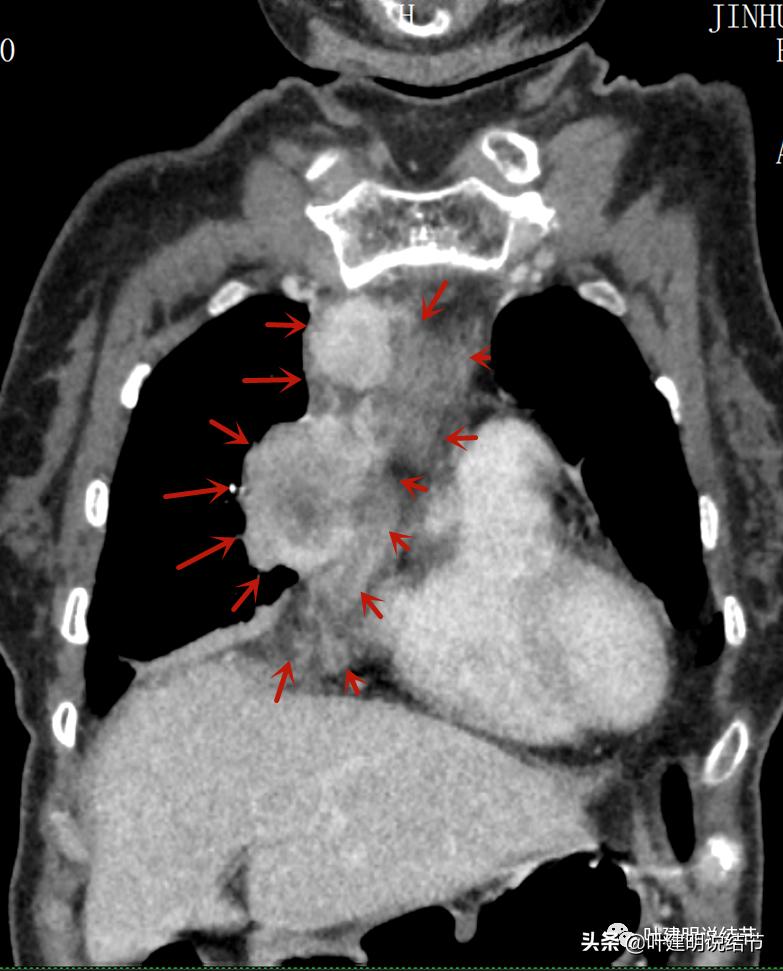

再来看看她的CT增强图像:

以下图片左侧是肺窗,右侧是纵隔窗。红色箭头示病灶,桔色箭头示无名静脉,黄色箭头示支气管,砖色箭头示上腔静脉,蓝色箭头示主动脉,紫色箭头示肺动脉。

病灶最大横断面水平,在冠状位上显示病灶多个中心似的,从上到下纵隔都有

病灶占据前纵隔从上到下全程,多中心,密度不均,对心脏与大血管有压迫,没有明显侵犯

病灶表面不平,中间有坏死

上图示最大横断位达5厘米